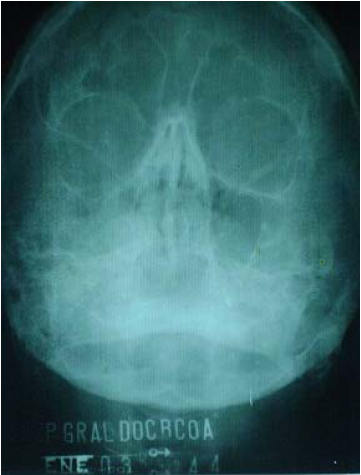

La radiografía de senos perinales realizada (Figura 3) denotó ligera radioopacidad y disminución del seno maxilar derecho.